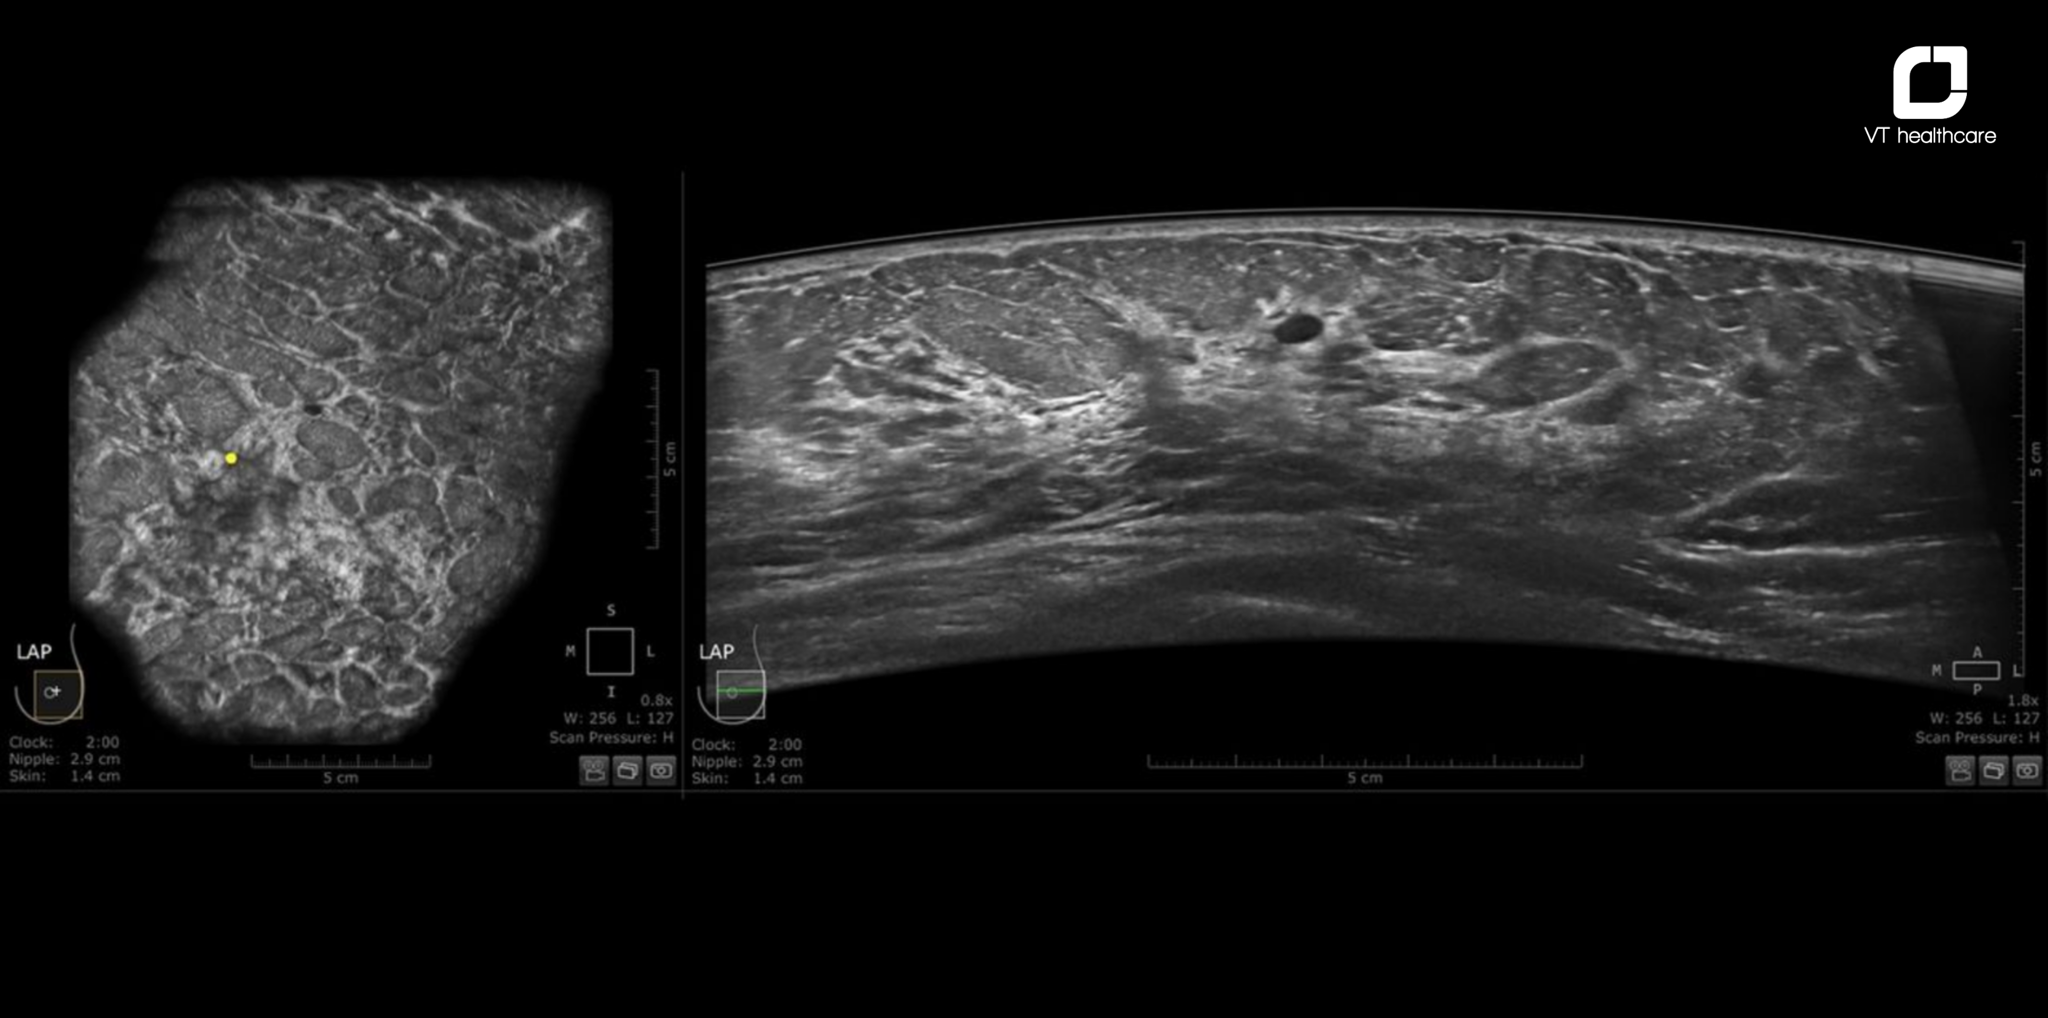

Invenia ABUS Prime (Automated Breast Ultrasound System) là hệ thống siêu âm vú 3D tự động do GE HealthCare phát triển, được thiết kế chuyên biệt để giải quyết những hạn chế của cả mammography lẫn siêu âm 2D trong đánh giá phụ nữ có mô vú đặc.

- Quét 3D tự động toàn bộ mô vú: Đầu dò thông minh tự động quét toàn bộ tuyến vú theo lộ trình chuẩn hóa, dựng lại hình ảnh 3D chi tiết đến từng lớp mô, loại bỏ sự phụ thuộc vào thao tác thủ công, đảm bảo tính nhất quán và khả năng tái lập kết quả.

- Lát cắt Coronal - góc nhìn độc đáo: Hình ảnh mặt phẳng vành (coronal plane) cho phép bác sĩ quan sát xuyên suốt từng lớp mô vú từ da đến thành ngực – góc nhìn không thể có trên siêu âm 2D thông thường, giúp phát hiện những tổn thương nhỏ ở vị trí khó.